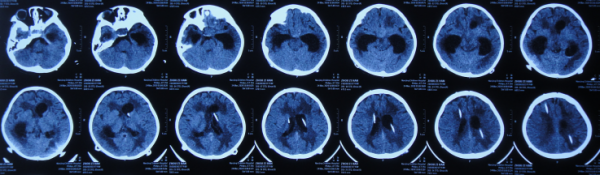

在第4家醫院治療26天期間內,三次複查頭部CT(圖-29、圖-30、圖-31)均示腦積水,右側顳角明顯擴。

圖-29:2020年4月23日頭部CT

圖-30:2020年5月7日頭部CT

圖-31:2020年5月18日頭部CT

看著患兒病情無好轉,家屬心急如焚,在網上找到李小勇腦脊液科經確認後於2020年5月19日(在第4家醫院治療26天)從安徽省蕪湖市轉入北京北亞骨科醫院的李小勇腦脊液科。

2020年5月19日(在半年時間內先後經4家醫院治療,即顱內腫瘤切除術後145天又即顱底腫瘤切除術後49天,仍反覆腦積水)轉入李小勇腦脊液科。入院時:體溫發熱38.5°C,意識模糊,左側肢體偏癱,體型偏瘦(圖-32)。

入院當天頭部CT示右側顳角擴張,腦室內有3根管(圖-33)。

圖-33:2020年5月19日頭部CT